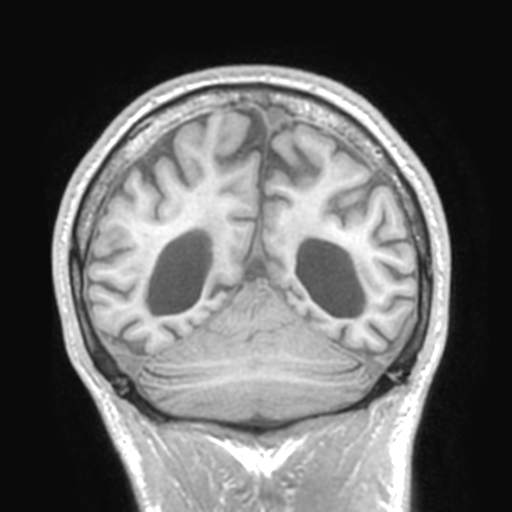

菱脑融合畸型